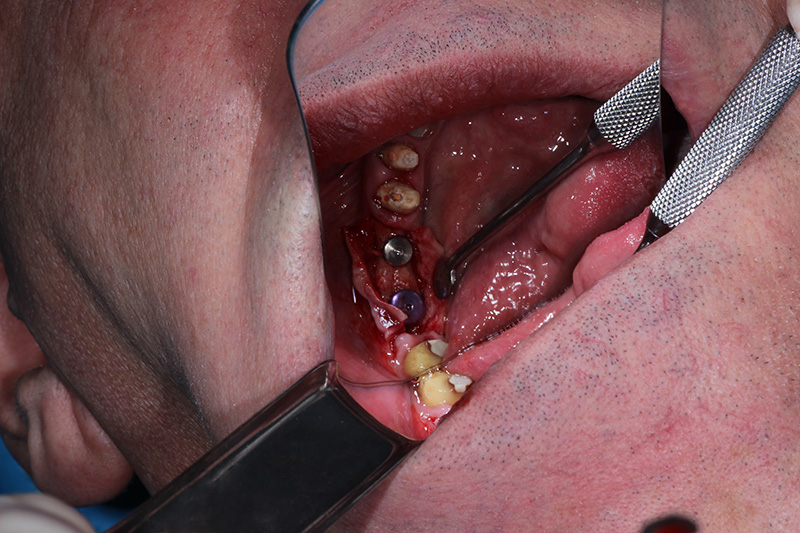

26-ого октября в учебном центре Стом-Лайн был проведен мастер-класс на тему «Закрытый и открытый синус-лифтинг при имплантации, с использованием имплантатов Thommen Medical». Мастер-класс провел главный врач-стоматолог клиники «Нюанс» в Москве Мхитар Казарян.

Мастер-класс начался с представления швейцарских имплантатов Thommen Medical, официальным предтсвителем которых является клиника Стом-Лайн. Далее были проведены обсуждения предстоящей операции и исследования компьютерной томографии, после чего участники смогли присутствовать на операции или следить за ней из учебного центра.

Во время операции доктор Казарян представил на практике особенности и преимущества имплантатов Thommen Medical.